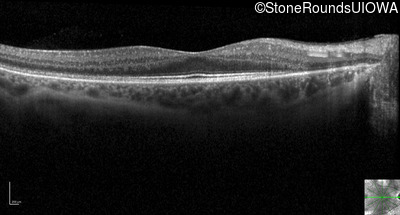

Optical Coherence Tomography - Right - 20/32 +2 sc

Exemplar / OCT Stack

OCT Stack